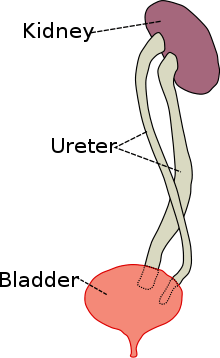

Duplicated ureter or Duplex Collecting System is a congenital condition in which the ureteric bud, the embryological origin of the ureter, splits (or arises twice), resulting in two ureters draining a single kidney. It is the most common renal abnormality, occurring in approximately 1% of the population.[1][2] The additional ureter may result in a ureterocele, or an ectopic ureter.

Ureteral development begins in the human fetus around the 4th week of embryonic development. A ureteric bud, arising from the mesonephric (or Wolffian) duct, gives rise to the ureter, as well as other parts of the collective system. In the case of a duplicated ureter, the ureteric bud either splits or arises twice. In most cases, the kidney is divided into two parts, an upper and lower lobe, with some overlap due to intermingling of collecting tubules. However, in some cases the division is so complete as to give rise to two separate parts, each with its own renal pelvis and ureter.